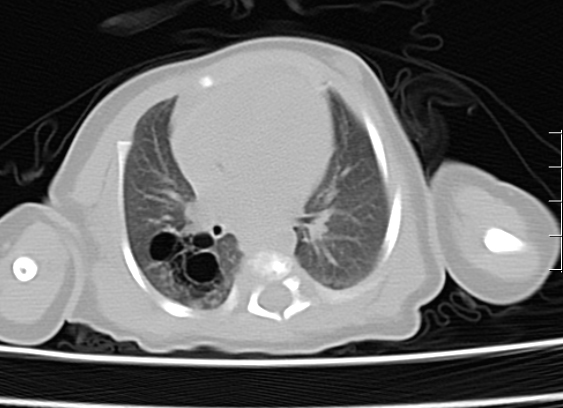

09-092024近日,我院PICU收治了一名先天性肺囊性腺瘤样畸形患儿,患儿母亲于孕22周产检时行超声检查发现胎儿存在该问题,胎儿期已诊断先天肺囊性腺瘤样畸形,在我院顺利生产,生后37天因并发感染于我院P...